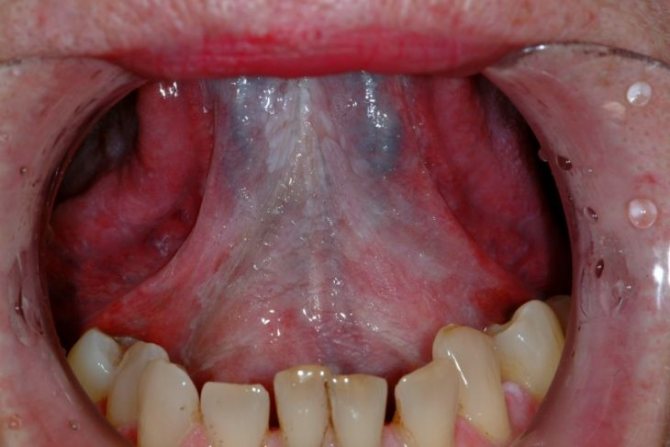

Фото лейкоплакии

Наиболее распространенными симптомами волосистой лейкоплакии языка являются:

- Появление белого налета в области основания языка и на его боковых поверхностях.

- На пораженных участках языка врач обнаруживает мелкие ворсинки.

- Очаги заболевания похожи на прозрачные или беловатые бородавки, длина которых, как правило, не превышает 1 сантиметра.

- Неоднородная поверхность слизистой.